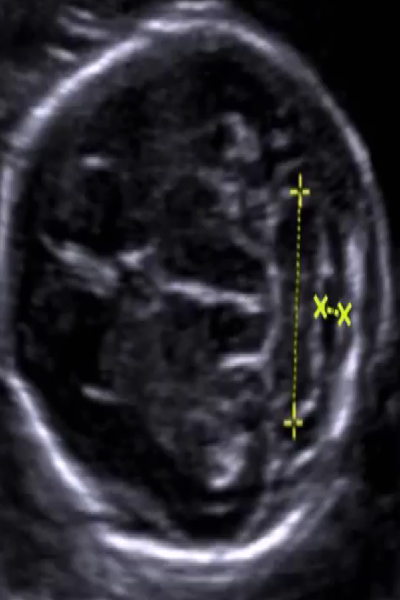

小脑横径

2021-10-22

14